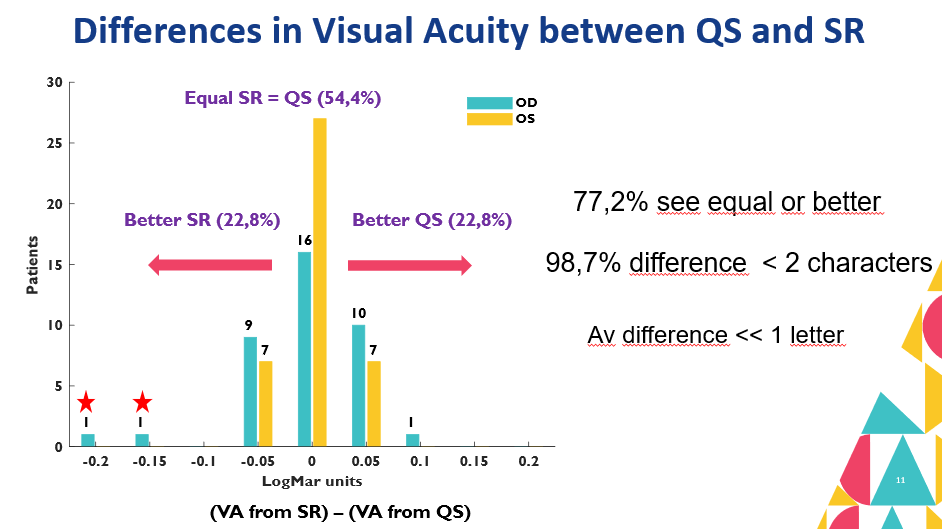

PurposeModern autorefractors have demonstrated high accuracy and higher repeatability than manifest refraction in adults yet are not considered precise enough to substitute the gold standard, even in low-resource settings where there is a severe shortage of experienced refractionists. This work evaluates a novel approach that combines dynamic wavefront aberrometry data, acquired using an affordable portable autorefractor, with the analysis of retinal image quality metrics (IQMs) to predict subjective refraction. Methods56 subjects (34±14 years) were recruited for the analysis. Each participant underwent standard clinical refraction followed by a 10-second video acquisition using a QuickSee (QS) wavefront aberrometer (PlenOptika, USA). Shack-Hartmann images of each video for the right eye were processed to obtain Zernike coefficients up to the 4th order. Coefficients obtained for each image were mathematically corrected with the closest sphero-cylindrical correction and the residual wavefront error was used to calculate the Point Spread Function (PSF) and IQMs (e.g., Strehl Ratio) describing some performance parameter of the corrected eye. Since each IQM is part of a dynamic sequence, it is possible to build a dynamic signal for each metric which contains information about fluctuations in image quality during the measurement. The final refraction is obtained as the average of the refractions corresponding to the images whose IMQs provided optimal performance. ResultsThe proposed method reduced the differences between QS and manifest refraction. Specifically, for spherical equivalent refraction (M) (Table 1) a 79% average reduction in MBE together with moderate average improvements for MAE (10.3%), LOA (5%), and percentage of agreement within 0.25D (8.8%) and 0.5D (6.3%) were found for all IQMs evaluated. ConclusionsThe proposed algorithm behaves as an efficient filter which selects those measurements within the dynamic sequence that are more representative of the manifest refraction of the patient. |

PurposeUncorrected Refractive Errors (UREs) is a reversible condition that can be treated with appropriate eyeglasses. UREs affect over 1 billion people globally, with 90% of this population living in low-and-middle-income countries where vision exams can be highly inaccessible due to a shortage of experienced eyecare professionals. This work aims to assess if a machine learning (ML) approach, when applied to data obtained with an affordable handheld autorefractor, could increase access to clinical-quality subjective refraction (SR) when operated by non-experts. MethodsData used for this analysis was obtained from a clinical study performed at Aravind Eye Hospital in Madurai, India, using a low-cost portable wavefront aberrometer, an early prototype of the QuickSee (QS) (PlenOptika, Inc., USA). A total of 669 participants were enrolled with ages ranging between 15 and 70 years (35.2 ± 13.7) and spherical equivalent error between -6.0 D and 3.5 D (-0.7 ± 1.67 D). Four ML regressor models were trained and tested for each power vector M, J0 and J45: random forest (RF), gradient boosting (GB), extreme gradient boosting (XGB), and a custom assembly model (ASB) that averages the predictions of RF, GB, and XGB. Algorithms were trained on a dataset of 1,244 samples using as input features: age, gender, Zernike coefficients up to 5th order, and measurement quality related metrics provided by the autorefractor. A smaller subset of 518 unseen samples was used to test the agreement of the predictions against SR using Bland-Altman analysis, overall prediction error in terms of mean absolute error (MAE) and root mean squared error (RMSE), and the percentage of agreement for 0.25 D and 0.5 D thresholds. ResultsAll models improved the agreement with SR compared to the baseline autorefraction, but ASB obtained the best results (Table 1). Bland-Altman analysis showed a decrease in the 95% limits of agreement of ±0.63 D, ±0.14 D, and ±0.08 D for M, J0 and J45, respectively. The wavefront-aberrometry related variables had the biggest impact on the prediction, while demographic and measurement quality-related features showed a heterogeneous but consistent predictive value. ConclusionsThese results suggest that ML is effective for improving precision in predicting patient’s SR from objective measurements taken with a low-cost portable device. |